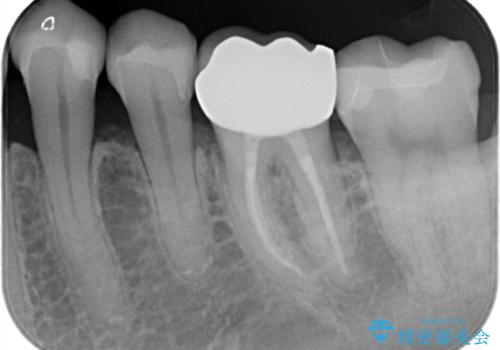

- 金属を外して白い歯を手に入れたいとのことで来院されました。

まとめて治療することで通院回数を減らすことができ、見た目も大変満足していただきました。

根管治療歯は破折防止のため速やかに被せ物が必要になります。